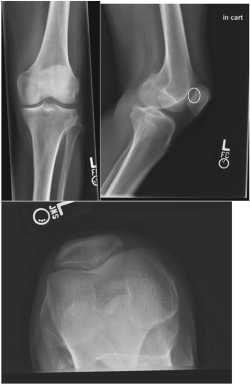

Radiographs, including anteroposterior, lateral, and sunrise views, were obtained and evident for a focal lucency of the posterior patella (see Figure 3). With this finding, it was recommended the patient to undergo MRI to confirm the presence of an OCD (see Figure 4), which was evident on that study.

Figure 3 - Click to enlarge in new windowFigure 3. Anteroposterior, lateral, and sunrise views of the left knee. On sunrise, note the lucency of posterior patella (ellipse), which is concerning for an osteochondral defect.